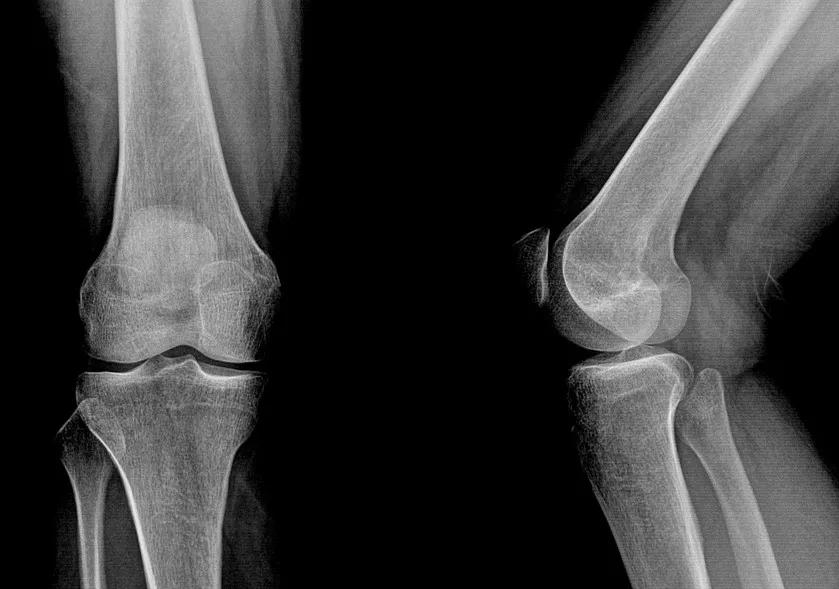

而膝关节几乎就是两个平面贴在一起

单靠骨头几乎没有稳定性

其稳定性全靠关节内外的韧带和肌肉